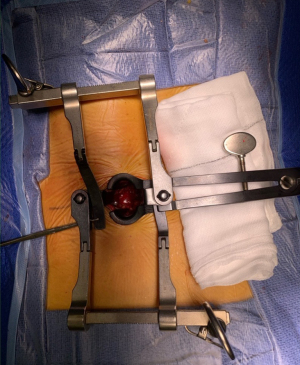

An initial Aesculap microdiscectomy retractor was placed, flat blade facing laterally, curved ones superior and inferior. Flat lateral blade was usually about 1–2 cm longer than cranio-caudal blades to help retract muscle over inter-transverse membrane.

A second lateral blade from another Aesculap retractor (Figure 2) was then added to hold the medial muscle clear over the distal facet joint. This blade was shorter as it sits atop the facet joint. A pair of artery forceps was used to stabilise it under the arm of the other lateral blade.